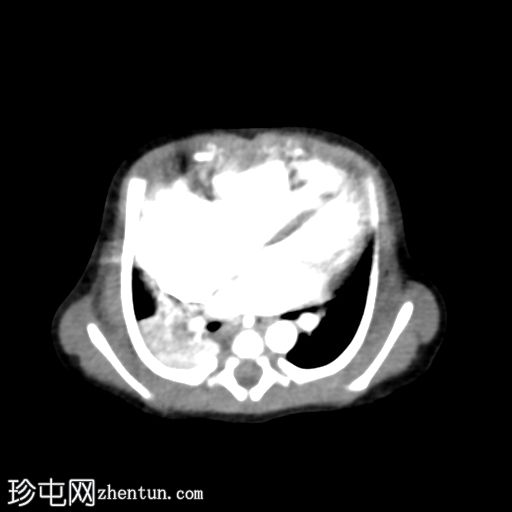

腹部

CT

1.jpg

轴向

非造影

2.jpg

轴向 C+

动脉期

3.jpg

冠状位

VR

脐区扩张的血管结构,由脐动脉(胎儿期)和两侧髂内动脉的分支以及上腹壁动脉供血。静脉引流经脐静脉,经静脉导管(胎儿期)流入左门静脉,随后流入下腔静脉。